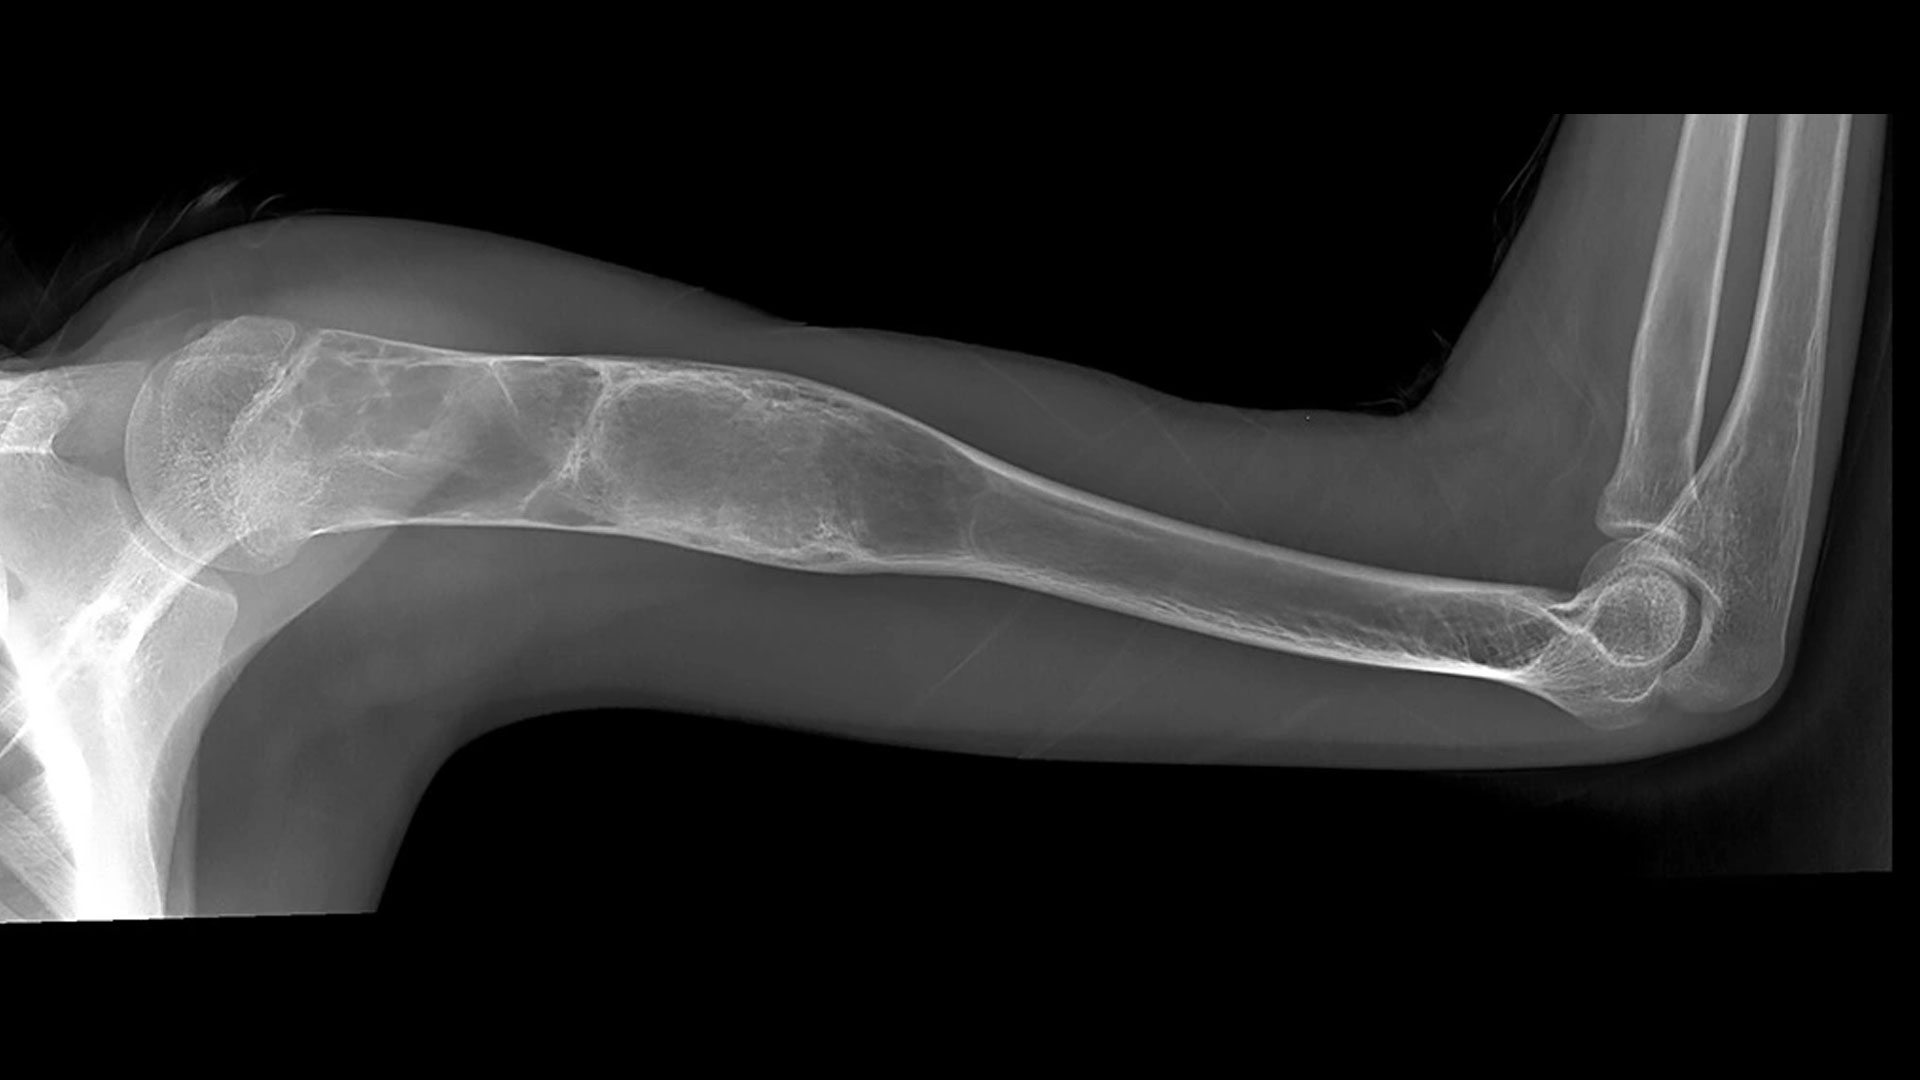

Bone tumors and bone cysts are abnormal growths that develop within the bone and may be benign (non-cancerous) or malignant (cancerous). Early diagnosis and accurate evaluation are critical to prevent bone damage, fractures, and long-term functional impairment.

Symptoms may include persistent bone pain, swelling, localized tenderness, restricted movement, or fractures occurring with minimal trauma. In some cases, bone tumors or cysts are detected incidentally during imaging for unrelated problems.

These conditions may arise due to abnormal bone cell growth, developmental bone changes, genetic factors, or unknown causes. Timely evaluation by Dr. Sourabh Jatkar helps distinguish benign from serious conditions.